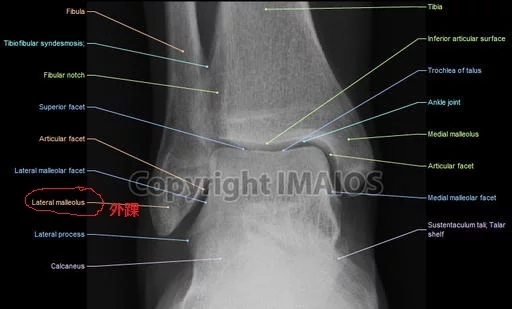

外踝

• 中文名 外踝

• 释    义 指腓骨下端向外的骨突

• 分    类 解剖结构名

• 又名 核骨

外踝(Malleolus lateralis),解剖结构名。出《灵枢·骨度》。又名核骨。指腓骨下端向外的骨突。